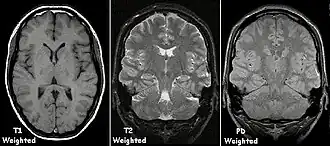

T1 and T2

Each tissue returns to its equilibrium state after excitation by the independent relaxation processes of T1 (spin-lattice; that is, magnetization in the same direction as the static magnetic field) and T2 (spin-spin; transverse to the static magnetic field). To create a T1-weighted image, magnetization is allowed to recover before measuring the MR signal by changing the repetition time (TR). This image weighting is useful for assessing the cerebral cortex, identifying fatty tissue, characterizing focal liver lesions, and in general, obtaining morphological information, as well as for post-contrast imaging. To create a T2-weighted image, magnetization is allowed to decay before measuring the MR signal by changing the echo time (TE). This image weighting is useful for detecting edema and inflammation, revealing white matter lesions, and assessing zonal anatomy in the prostate and uterus.

The standard display of MR images is to represent fluid characteristics in black-and-white images, where different tissues turn out as follows:

| Signal | T1-weighted | T2-weighted |

|---|---|---|

| High |

|

| Intermediate |

| Low |